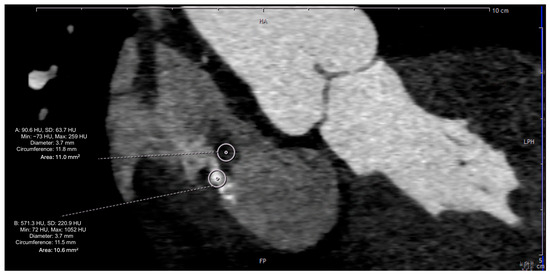

2. Case Presentation